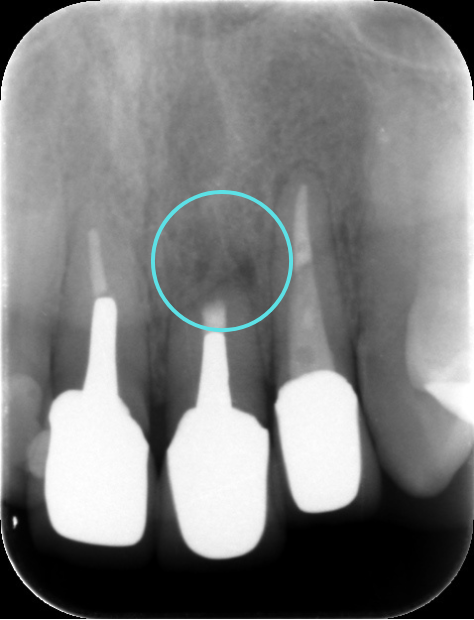

術後すぐ

術後3ヶ月のレントゲン写真

術後1年のレントゲン写真

根尖病変によって骨が溶かされてしまった空間も、歯根端切除術によって感染源が適切に除去され、根管が緊密に封鎖されると、体本来の治癒力によって再び新しい骨(新生骨)が作られていきます。 レントゲンでは、術直後は黒い影(骨がない状態)だった部分が、時間の経過とともに徐々に白く(骨が再生してきた状態)映るようになります。この「新生骨の出現」が、外科的歯内療法の成功を示す客観的な証拠となります。

今回の患者さんも、術後の定期検診にお越しいただきました。 術後6ヶ月の時点でのレントゲン写真では、手術前に黒い影として見えていた根尖病変部、および歯根を切除したスペースに、白く不透明な影、すなわち「新生骨」が順調に再生してきていることが明確に確認されました。